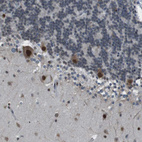

Immunohistochemical staining of human cerebral cortex shows strong cytoplasmic and nuclear positivity in neurons.